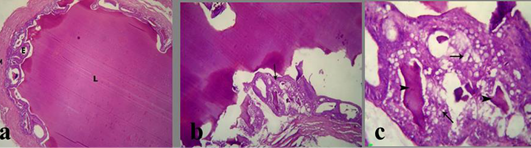

Figure 4: a) Section in Seminal vesicle of the control male albino rat showing normal lumen filled with eosinophilic fluid (L), secretory epithelium (E) and muscular coat (M); b, c) treated mature male albino rat orally administrated crude extract of Euphorbia peplus at dose level of 500mg/kg b.wt twice weekly for 65 days showing severe vacuolation of lining epithelium (arrows) and scanty insipisated secretion (arrowheads)